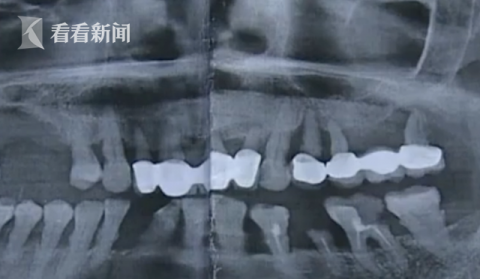

对此 , 余杭区第五人民医院口腔科副主任汪医生向采访人员展示了朱阿姨的口腔拍片结果 , 他表示当事医生的处理没有问题 , 被拔掉的几颗牙齿都是有问题的 , 没必要保留 , 而且拔牙之前也跟朱阿姨沟通过这个情况 。 医院医务处工作人员称 , 希望能和朱阿姨够通过医学鉴定来解决此事 。 目前 , 此事仍在协调阶段 。